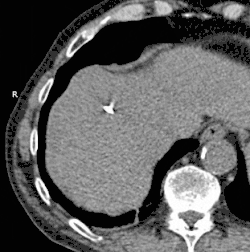

L'application la plus commune de la cryoablation consiste à éliminer les tumeurs solides trouvées dans les poumons, le foie, le sein, et plus couramment dans les reins et la prostate. Bien qu'appliquée par des approches chirurgicales laparoscopiques ou ouvertes notamment en cryochirurgie, la cryoablation est le plus souvent réalisée par voie percutanée (à travers la peau et dans le tissu cible contenant la tumeur) par un médecin spécialiste, tel qu'un radiologue interventionnel.

La cryoablation a été explorée comme alternative à l'ablation par radiofréquences dans le traitement de la douleur modérée à sévère chez les personnes atteintes d'une maladie osseuse métastatique. La zone de destruction tissulaire créée par cette technique peut être surveillée plus efficacement par tomodensitométrie que par RFA, un avantage potentiel lors du traitement de tumeurs adjacentes à des structures critiques[10].